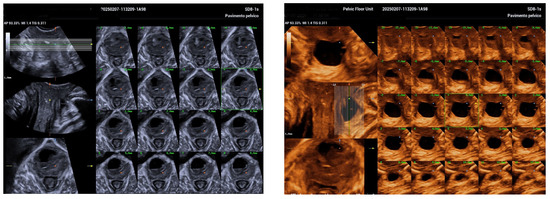

2. Case Report

| Jeong et al. [5] | Suprapubic pain, purulent discharge, leakage | 5.5 cm | TVUS, TPUS, 3D ultrasound at 34 weeks | Antibiotics; aspiration considered | Planned vaginal delivery | Postpartum diverticulectomy |